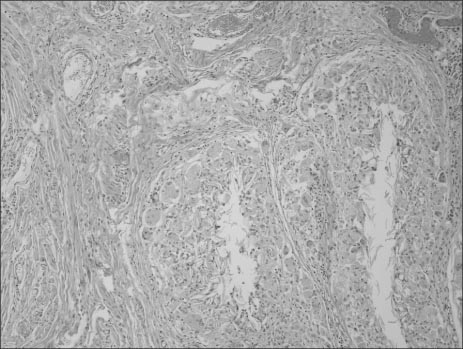

Fig. 5

Some part shows the granulomatous foreign body reaction (H&E, ×100).